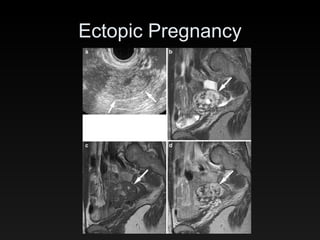

Ectopic Pregnancy 24 pregnant female pts with suspected EP (18 had vaginal spotting & pain) US showed absence of IUP in all pts (# of EP’s found by US not mentioned) Of 19 EP’s, MR found 18 (1 FN, no FP) MR sens 95%, spec 100%, acc 96%

Ectopic Pregnancy